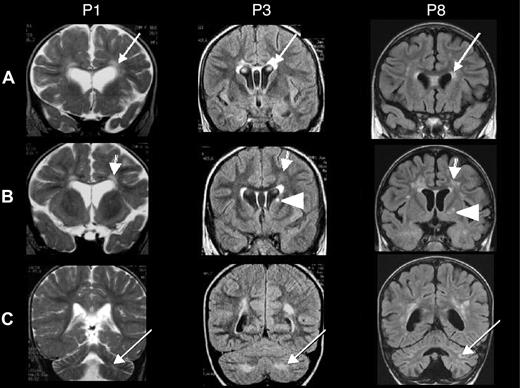

Of the 7 patients with neurologic HLH before HSCT, 3 patients (P4, P6, and P7) died shortly after HSCT. Two of the 7 patients (P2 and P5) have not shown any neurologic sequelae 9 and 4 years after HSCT, respectively. In contrast, 2 patients (P3 and P8) exhibited the following neurologic sequelae after HSCT: P3 showed impaired cognitive abilities with a clinically estimated developmental age of 5 years for a chronologic age of 7. Brain MRI showed abnormal hyperintensities in the periventricular white matter and signal abnormality in the caudate nucleus (Figure 1 middle panel). P8 continues to suffer from pharmacologically resistant epilepsy and also presents ataxia. Brain MRI showed cerebellar and periventricular white matter lesions and signal abnormality in the putamen (Figure 1 right panel). Furthermore, P1 (having suffered from neonatal-onset HLH, but who had not presented any neurologic involvement before HSCT) developed cognitive difficulties after HSCT and showed a clinically estimated developmental age of 3 years for a chronologic age of 6.5. Here again, brain MRI showed white matter abnormalities in the periventricular and cerebellar areas (Figure 1 left panel). Taken together, of the 7 patients who survived, 4 patients (P2, P5, P9, P10) were cured without neurologic sequelae with a mean follow-up after HSCT of 4 years (range, 10 months to 9 years).

Brain MRIs of patients 1, 3, and 8. Coronal brain MRIs of patients P1 (taken at age 20 months, 11 months after HSCT), P3 (age 6 years, 2 months before HSCT), and P8 (age 3 years, 3 months after HSCT). T2-weighted images are shown for P1, and fluid attenuation inversion recovery (FLAIR) images are shown for P3 and P8. (A) Bilateral, abnormal hyperintensities in the periventricular white matter (arrows) and the anterior part of the corpus callosum. (B) Abnormal hyperintensities in the white matter, the periventricular area but not of the U fibers (arrows), and a unilateral signal abnormality in the basal ganglia (the caudate nucleus in P3 and the putamen in P8; arrowheads). (C) White matter abnormalities in the cerebellum (arrows).